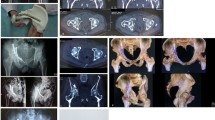

Different methods and technique are available for 3D printing of medical models. For this study, the anonymized CT scans with fine-cut (< 1 mm) resolution of the selected cases were downloaded as DICOM images and outsourced to a third party company for 3D printing. They reconstructed the computer generated 3D model via a custom built SLA 3D printer using photopolymer material. Processing was performed using the ScanIP (synopsis) software and the photopolymer models were printed using custom-built SLA (Stereolithography) 3D printer (Fig. 2) with each model costing between US$ 350 – 400.

The transverse and both column fracture patterns were easiest to diagnose. The number of candidates who could correctly identify each fracture type in post-test was higher in the 3D model group when compared to the conventional lecture group especially for more complex 'associated' fractures (Fig. 2). Posterior column fracture diagnosis improved from 0 in either group to 50% (4 out of 8) and 75% (6 out of 8) in respective groups (Fig. 2). When clubbed into 'elementary' and 'associated' fractures for analysis, 40% improvement incorrect diagnosis was seen for group 2 (Table 3).

The ability to plan the correct surgical approach depends not only on the correct identification of fracture but understanding the fracture pattern. Candidates were deemed proficient if they could propose a correct surgical approach for least 75% of cases; which in our study was considered as of 7 out of 10 cases. Fifty per cent (4 out of 8) in Group 1 showed this proficiency compared to 100% (8 out of 8) in Group 2 after exposure to the teaching method (Fig. 3 and 4).